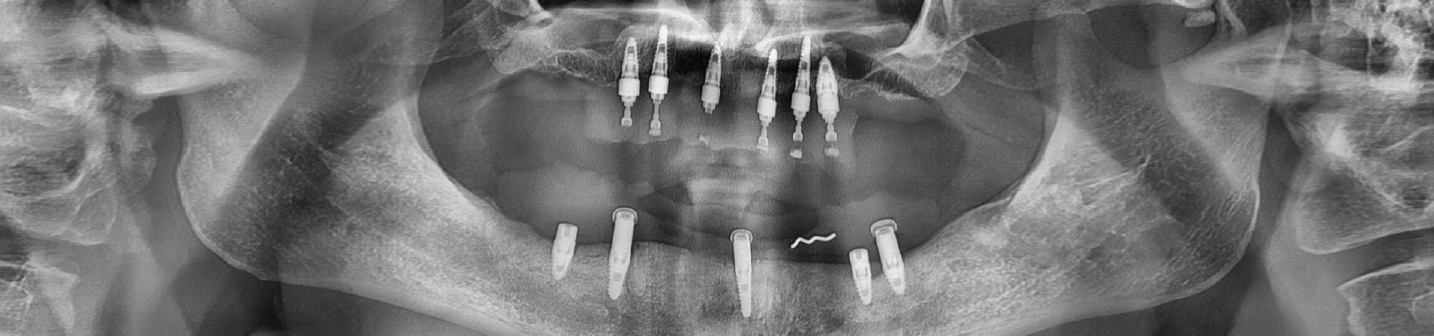

Hybrid Denture

Hybrid implant denture is a combination between both dental implants and traditional dentures. Hybrid denture is a full set of replacement teeth resting on dental implants (implant supported denture). With the arrival of the solid zirconia full-arch implant retained prosthesis we now have a prosthetic option that offers the stability and performance of dental implants with better cost.

Avoiding disadvantages of conventional dentures, hybrid dentures give better, non-fake appearance and are easier to maintain. Just like your natural teeth you need to brush them twice daily. Hybrid dentures are designed to be securely fit, fixed in place and permanent so they can only be removed by the dentist.